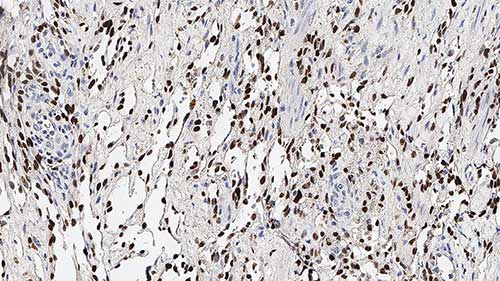

Human colon, gastrointestinal stromal tumor: immunohistochemical staining for DOG-1. Note membrane staining of neoplastic cells. DOG-1: clone K9

DOG-1, uma proteína de 986 aminoácidos de função desconhecida, é expressa predominantemente na membrana plasmática de tumores estromais gastrointestinais (GIST) e raramente expressa em outros tumores de tecido moles, que, devido à aparência, podem ser confundidos com GIST.

Imunorreatividade para DOG-1 tem sido relatada ser encontrada em 97,8% dos GIST contáveis, incluindo todos os GIST KIT negativos.

Reatividade para DOG-1 tem sido sugerida para auxiliar na identificação de GIST, incluindo as mutações do alfa receptor do fator de crescimento derivado de plaquetas que não conseguem expressar antígeno KIT.